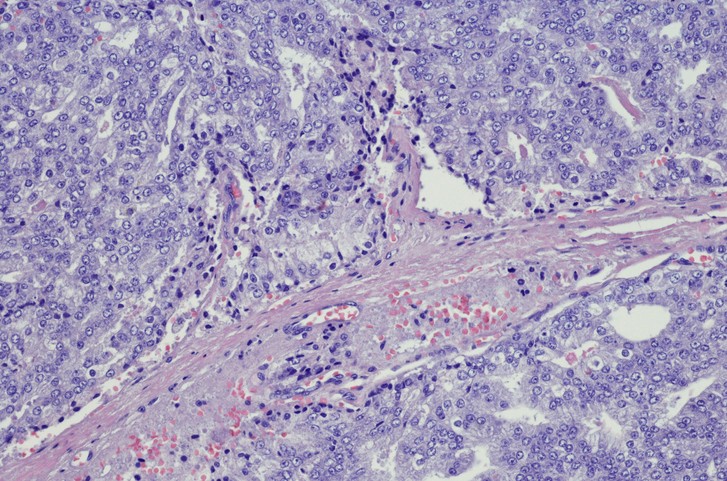

Featured photo at top of prostate cancer cells. Photo/iStock/OGphoto.